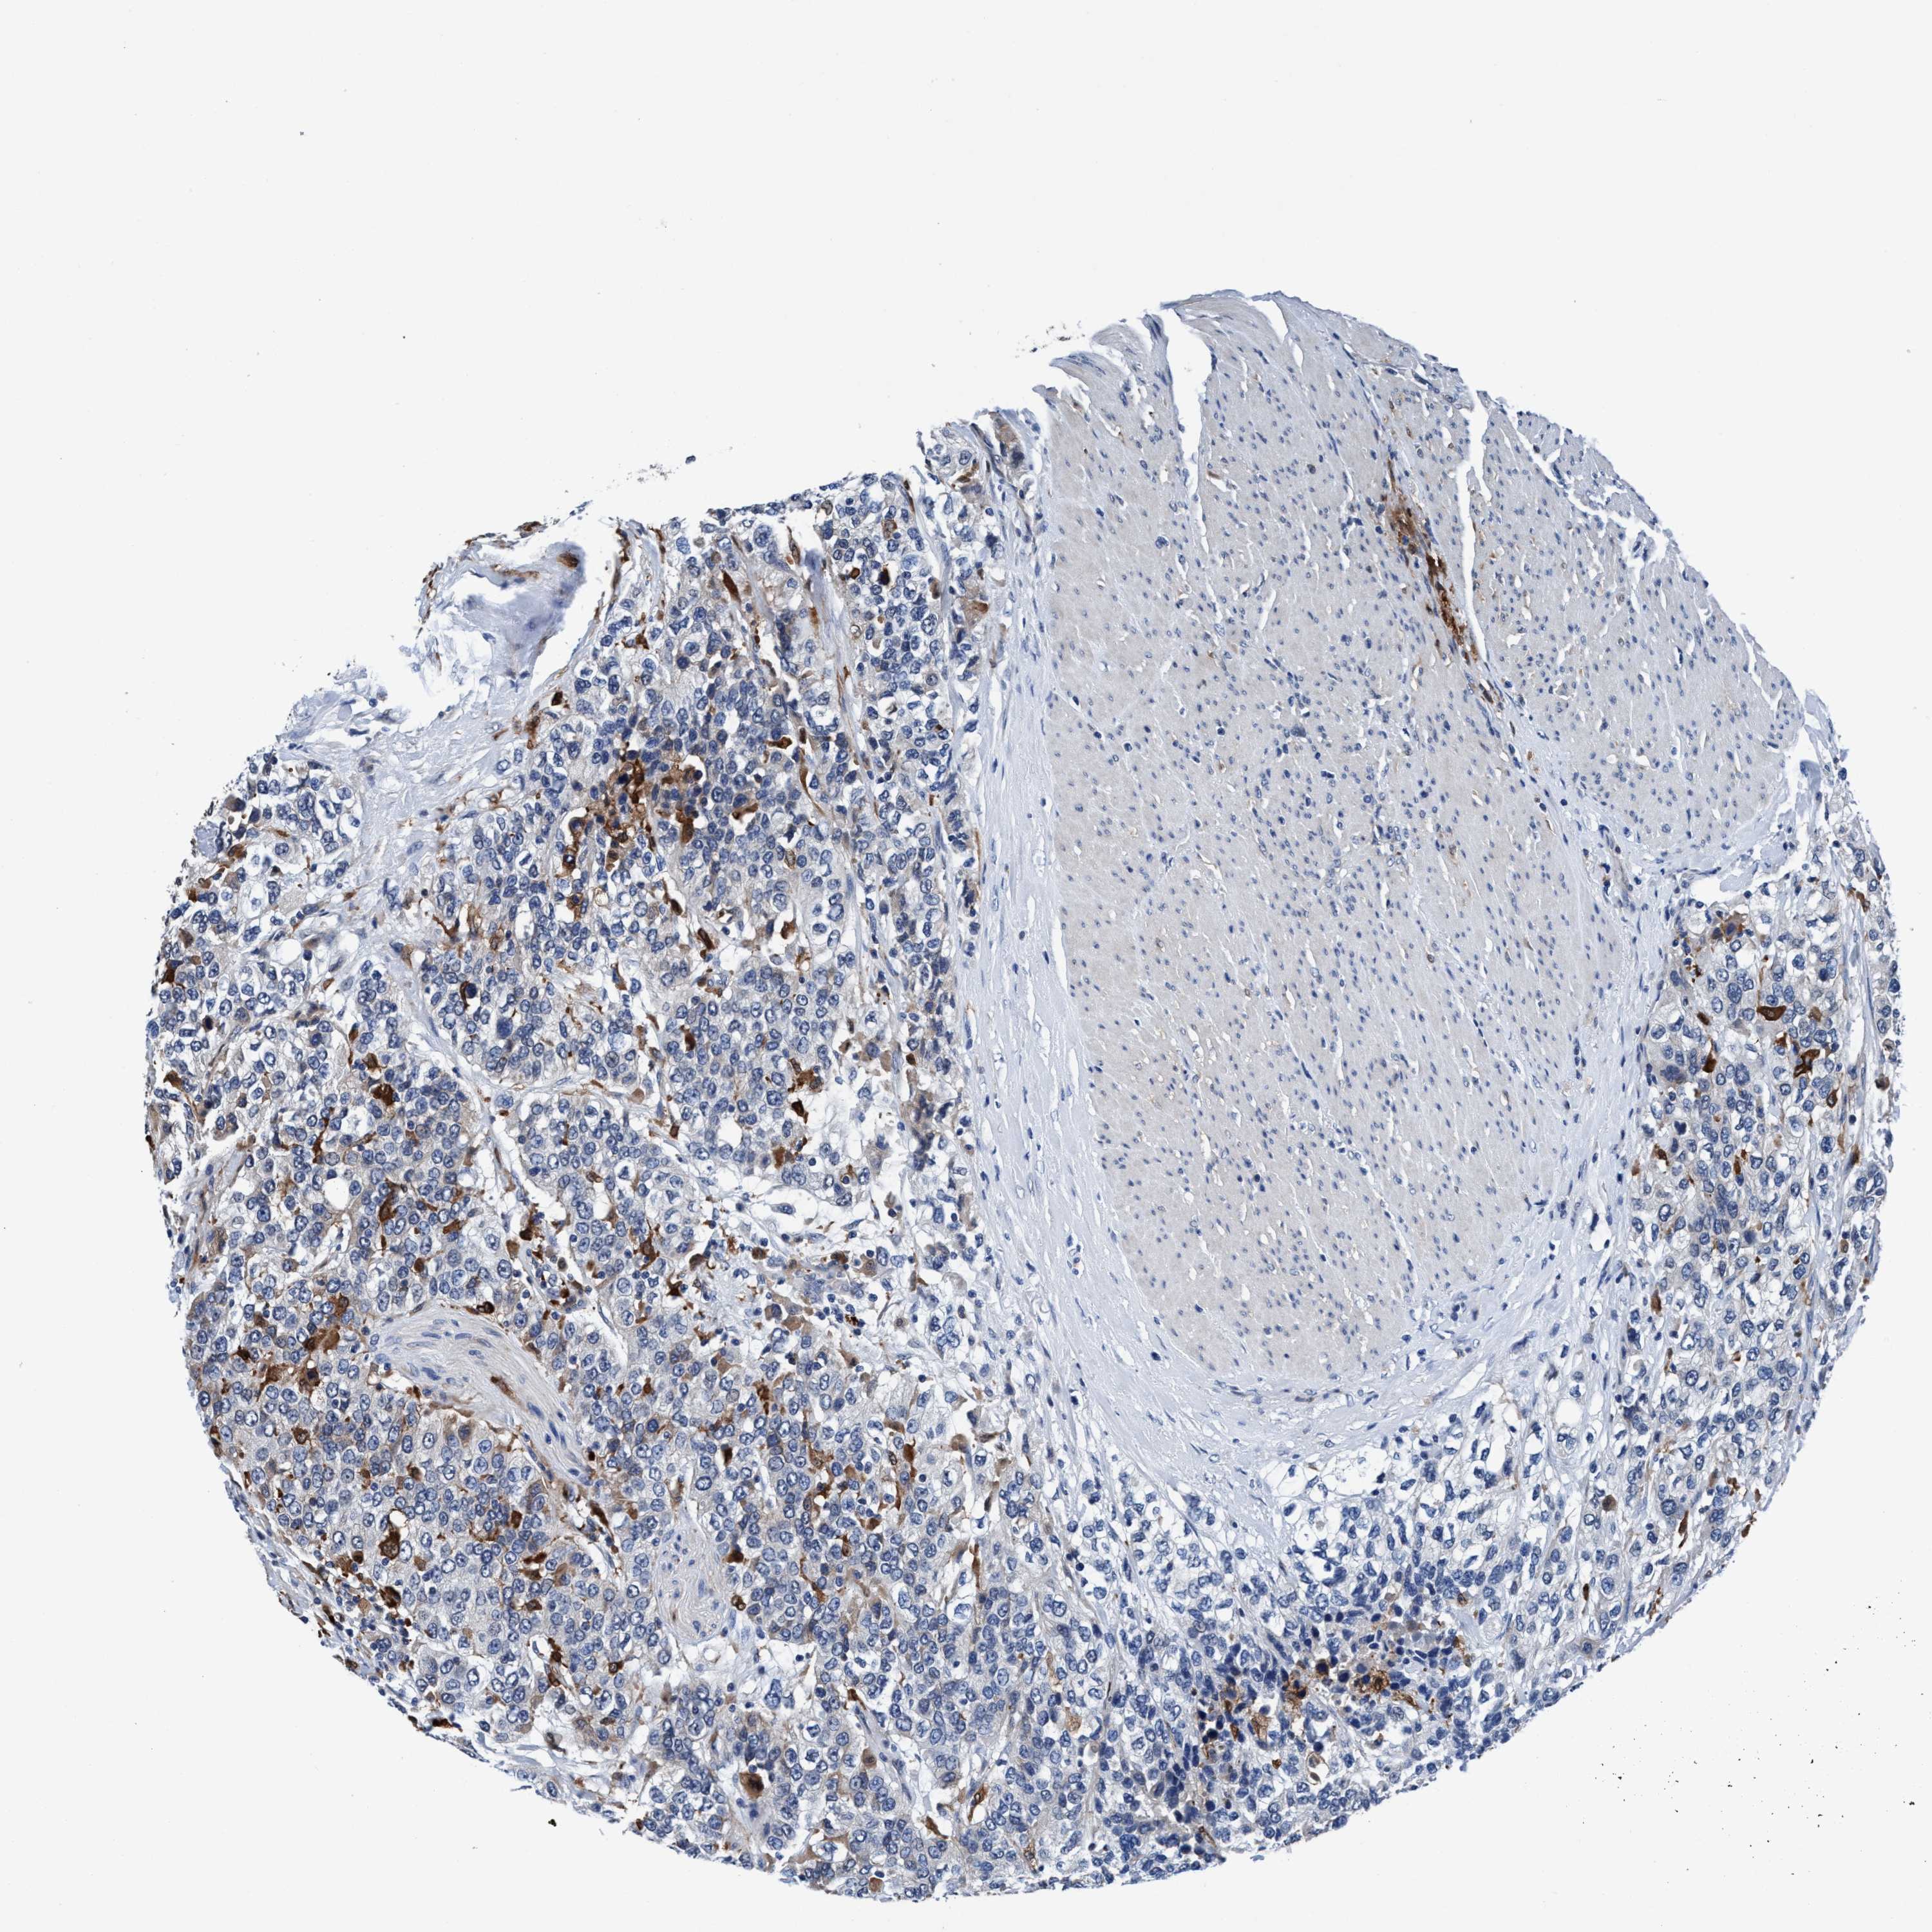

UROTHELIAL CANCER - Protein expressioni

A mouse-over function shows sample information and annotation data. Click on an image to view it in a full screen mode. Samples can be filtered based on level of antibody staining by selecting one or several of the following categories: high, medium, low and not detected. The assay and annotation is described here.

Note that samples used for immunohistochemistry by the Human Protein Atlas do not correspond to samples in the TCGA dataset.

Antibody stainingi

Antibody staining in the annotated cell types in the current human tissue is reported as not detected, low, medium, or high, based on conventional immunohistochemistry profiling in selected tissues. This score is based on the combination of the staining intensity and fraction of stained cells.

Each image is clickable and will lead to virtual microscopy that enables deeper exploration of all samples and also displays staining intensity scores, fraction scores and subcellular localization as well as patient and tissue information for each sample.

Antibody HPA008423

Staining

High

Medium

Low

Not detected

Intensity

Strong

Moderate

Weak

Negative

Quantity

>75%

75%-25%

<25%

None

Location

Urothelial carcinoma, Low grade

Urothelial carcinoma, High grade